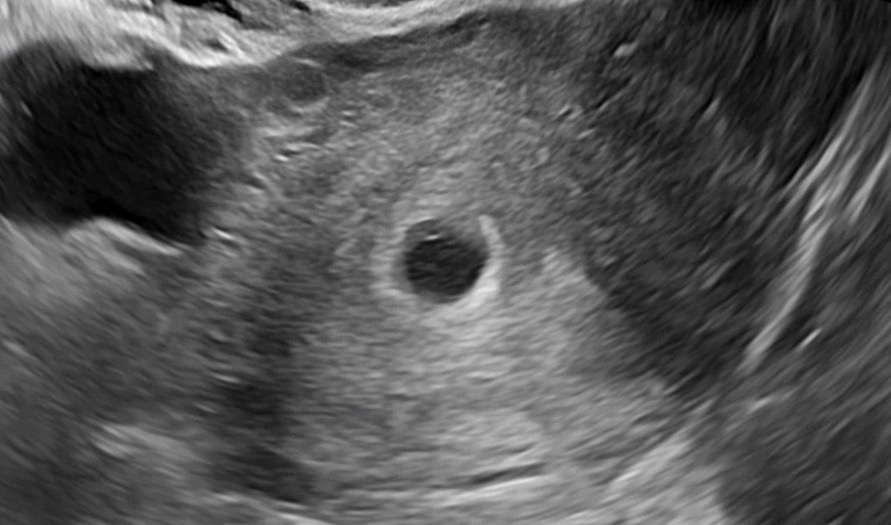

난황 생기려고 하는걸까요?

저 하얀 손톱같은 부분이 난황 생기려고 하는걸까요?? ㅠㅠ